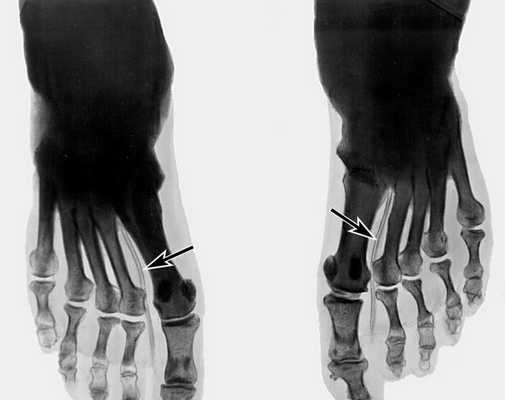

Самым достоверным способом диагностики М.с. является рентгенография нижних конечностей, которую проводят в прямой и боковой проекциях. При этом на обзорном снимке удается проследить весь ход артериального русла ноги от уровня подколенной артерии и ниже, иногда вплоть до мелких артерий стопы. Плотность пораженной артерии на рентгенограмме почти равна плотности костной ткани (рис.

). Артериография нижних конечностей позволяет документально подтвердить наличие окклюзии сосуда при М.с. и установить ее уровень, а также оценить состояние коллатералей.

Самым достоверным способом диагностики М.с. является рентгенография нижних конечностей, которую проводят в прямой и боковой проекциях. При этом на обзорном снимке удается проследить весь ход артериального русла ноги от уровня подколенной артерии и ниже, иногда вплоть до мелких артерий стопы. Плотность пораженной артерии на рентгенограмме почти равна плотности костной ткани (рис.). Артериография нижних конечностей позволяет документально подтвердить наличие окклюзии сосуда при М.с. и установить ее уровень, а также оценить состояние коллатералей.

Рентгенограмма голеней больного со склерозом Менкеберга на фоне сахарного диабета: стрелками указаны кальцифицированные большеберцовые артерии">

Рис. б). Рентгенограмма стоп больного со склерозом Менкеберга на фоне сахарного диабета: стрелками указаны кальцифицированные артерии тыла стопы.